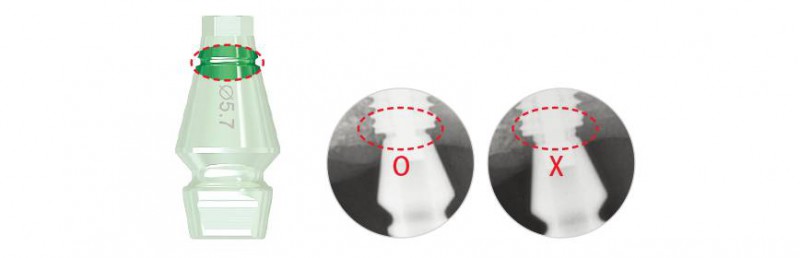

☆小提示:可通過X光片確認(rèn)代替體與印模轉(zhuǎn)移桿是否連接正確。